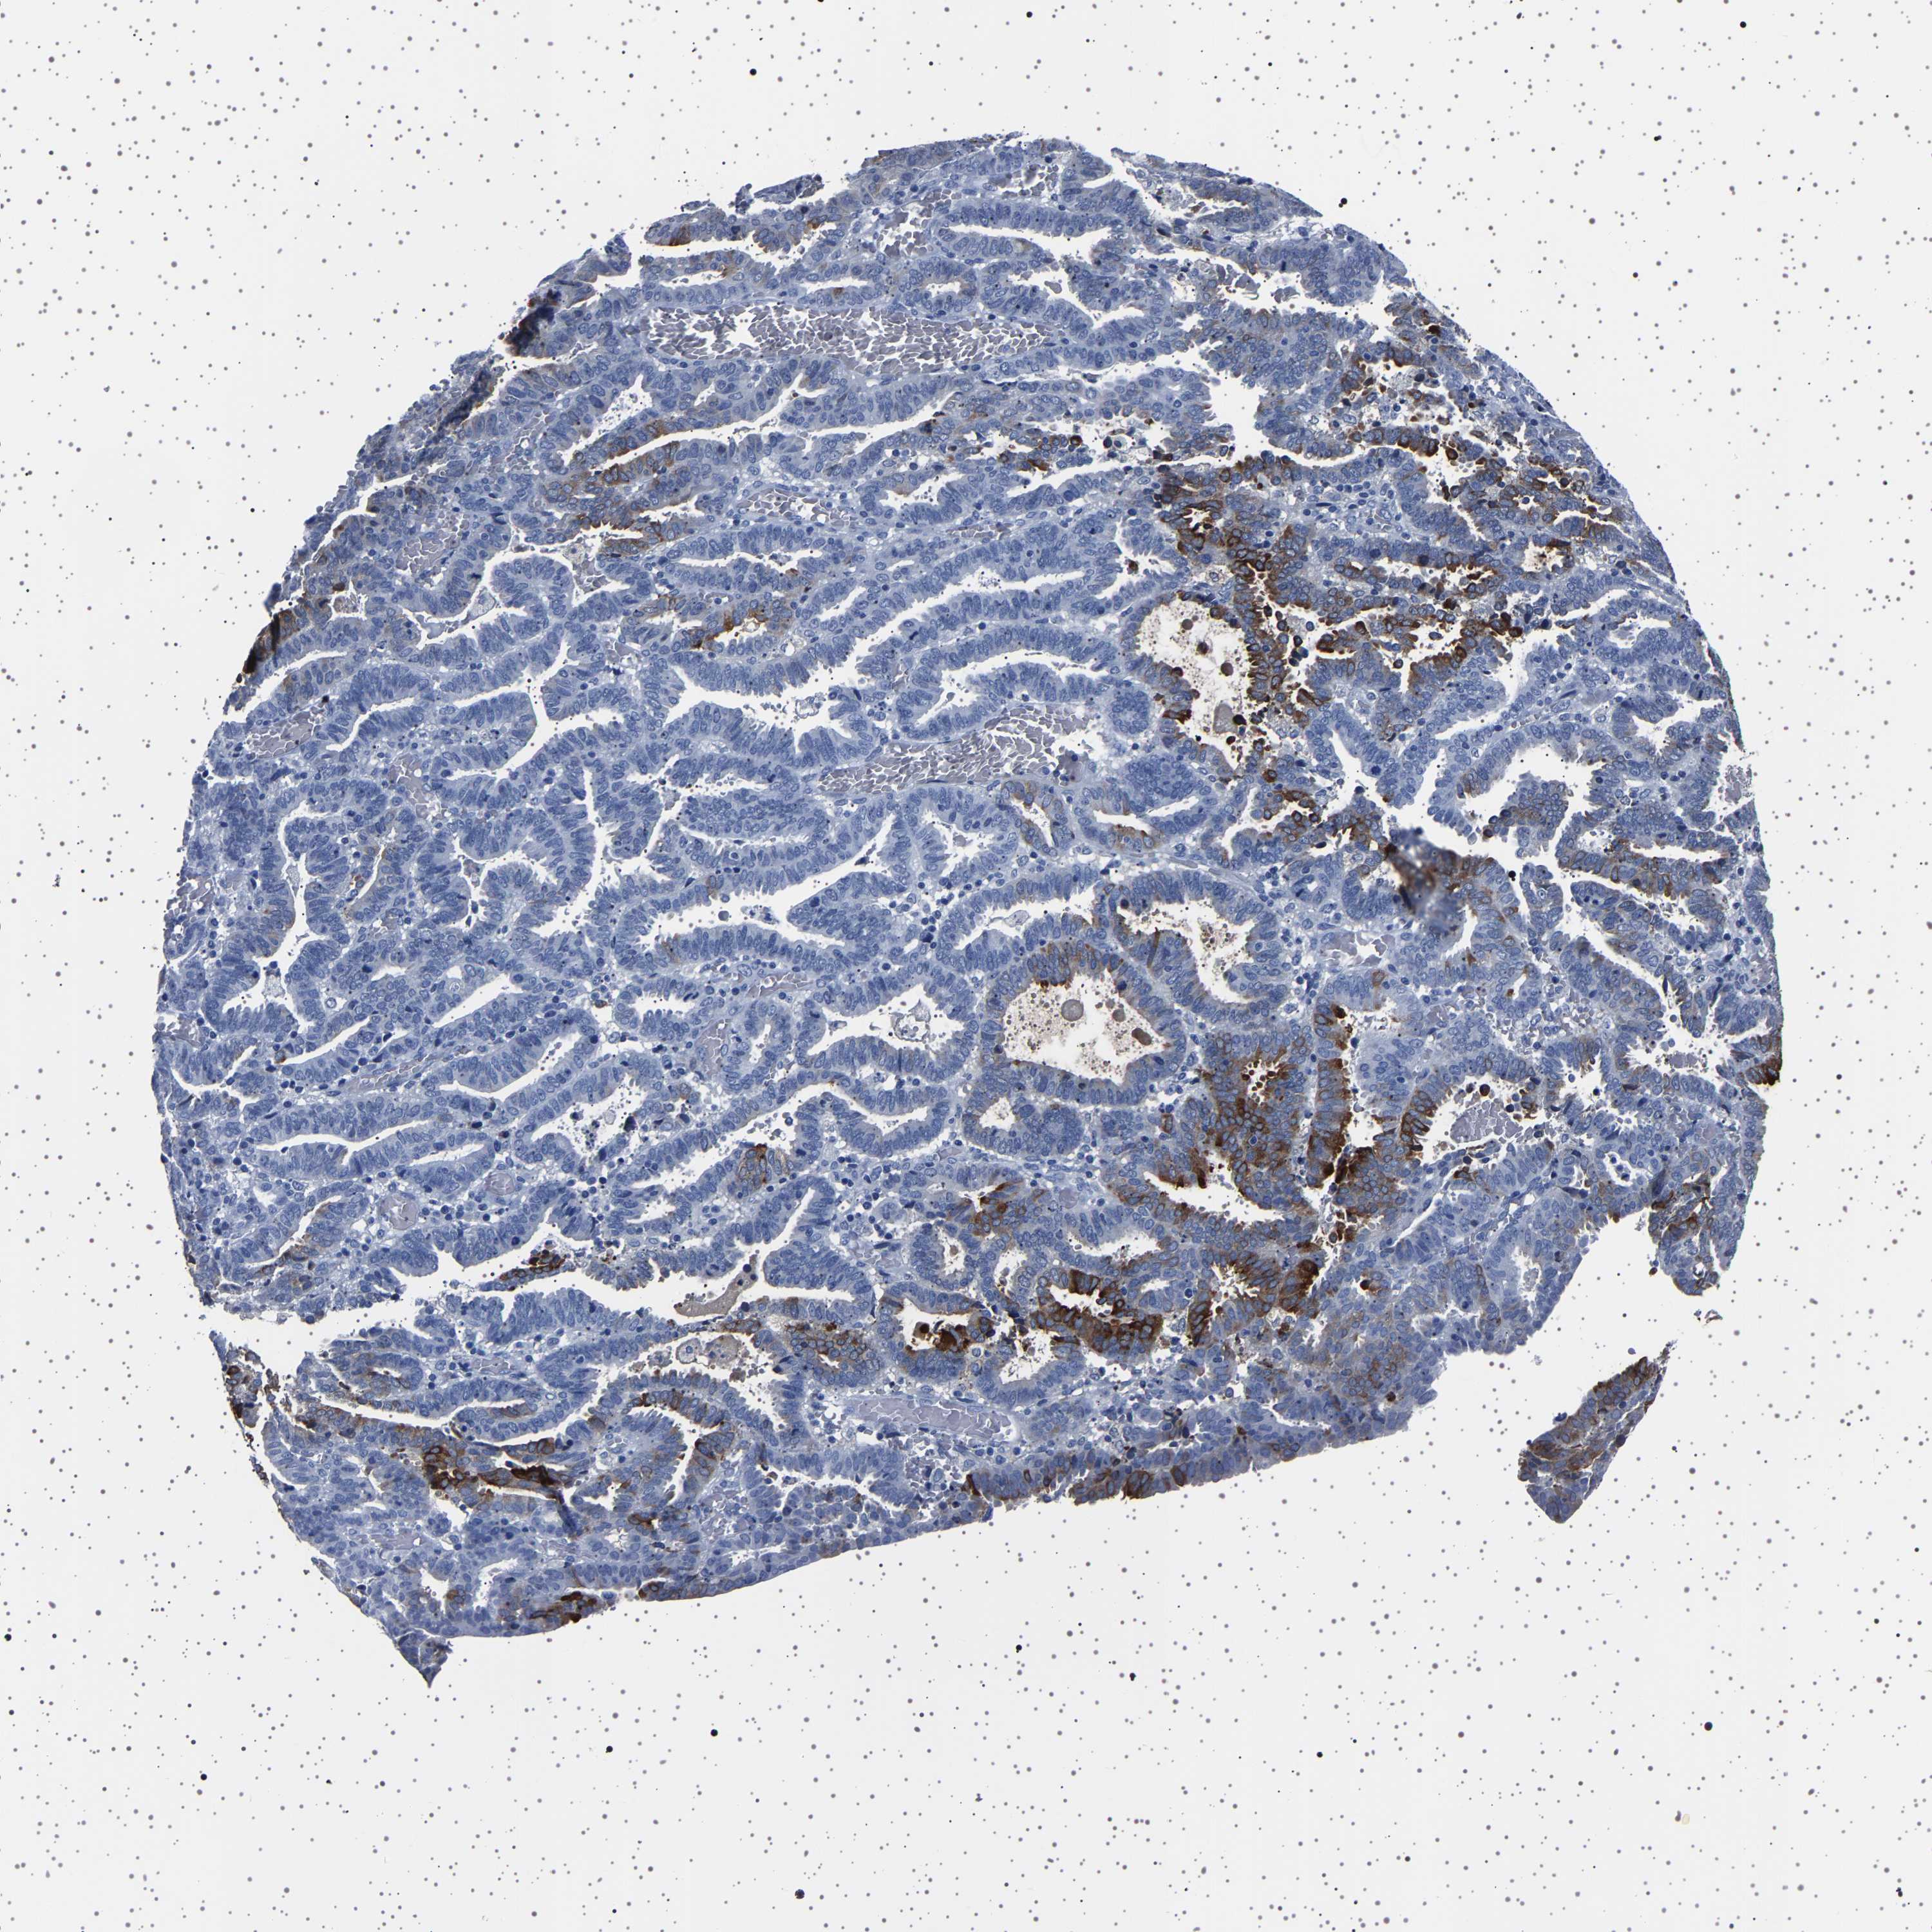

ENDOMETRIAL CANCER - Protein expressioni

A mouse-over function shows sample information and annotation data. Click on an image to view it in a full screen mode. Samples can be filtered based on level of antibody staining by selecting one or several of the following categories: high, medium, low and not detected. The assay and annotation is described here.

Note that samples used for immunohistochemistry by the Human Protein Atlas do not correspond to samples in the TCGA dataset.

Antibody stainingi

Antibody staining in the annotated cell types in the current human tissue is reported as not detected, low, medium, or high, based on conventional immunohistochemistry profiling in selected tissues. This score is based on the combination of the staining intensity and fraction of stained cells.

Each image is clickable and will lead to virtual microscopy that enables deeper exploration of all samples and also displays staining intensity scores, fraction scores and subcellular localization as well as patient and tissue information for each sample.

Antibody HPA035464

Antibody CAB020681

Staining

High

Medium

Low

Not detected

Intensity

Strong

Moderate

Weak

Negative

Quantity

>75%

75%-25%

<25%

None

Location

Nuclear

Cytoplasmic/membranous

Cytoplasmic/membranous,nuclear

Adenocarcinoma, NOS